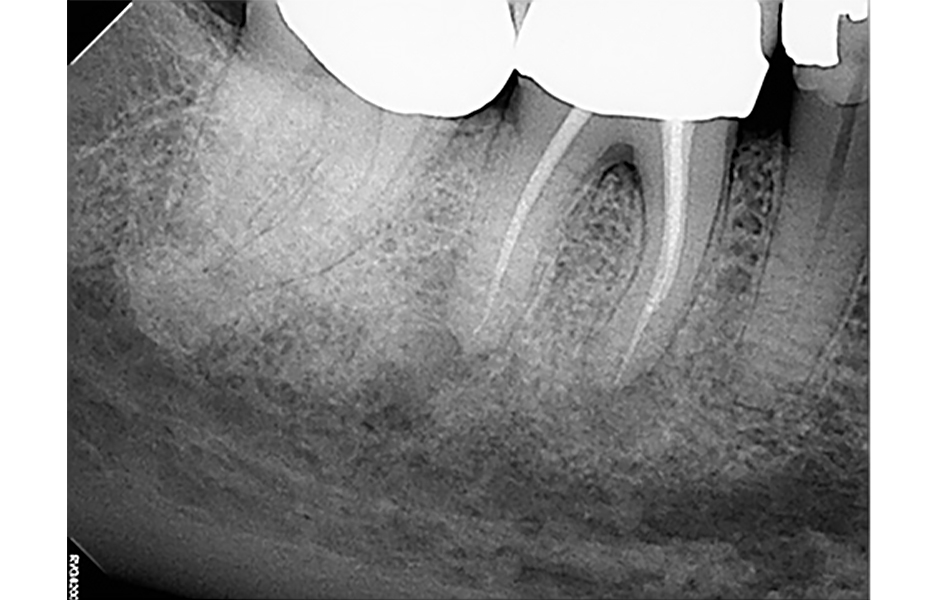

Pro radiologickou diagnostiku byl pořízen periapikální (PA) rentgenový snímek (obr. 1) a CBCT snímek s omezeným zorným polem (obr. 2a–d). Předchozí endodontické ošetření zahrnovalo zaplnění tří kanálků s nedostatečnou hustotou výplně v apikální třetině meziálních a distálních kořenů. V oblasti apexů meziálních (3 × 3 mm) a distálních (3 × 5 mm) kořenů byla patrná periapikální projasnění. CBCT (obr. 2a–d) potvrdilo nezaplněný distolingvální (DL) kanálek a možný střední meziální (MM) kanálek; koronální CBCT řez meziálního kořene (obr. 2c) také naznačuje přítomnost apikální delty spíše než jediného apikálního foramenu. Nebyly zjištěny žádné známky prasklin či fraktur.

Obr. 2a, b: Předoperační CBCT řezy zubu 46 – a) sagitální, b) axiální.